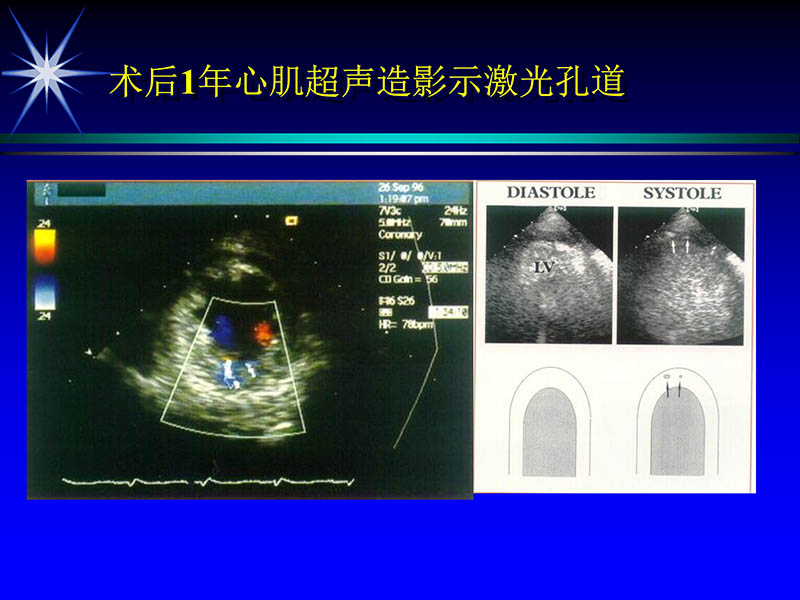

2004-06-15激光直接心肌血运重建治疗冠心病